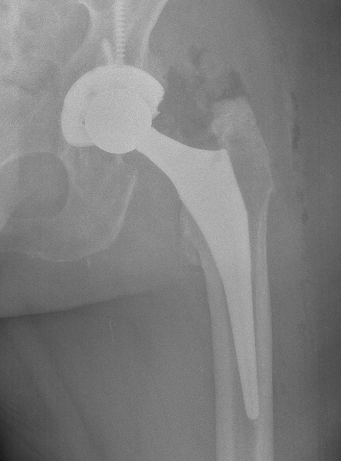

Brooker Classification: Type III and Type IV clinically relevant

Type I: Isolated islands of bone

Type II: Bony spurs from pelvis and proximal femur, gap > 1 cm

Type III: Gap < 1 cm

Type IV: Apparent ankylosis